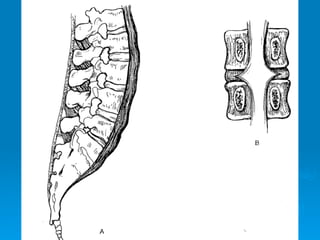

Mal de Pott

Enfermedades degenerativas

Discopatía lumbar

caso clinico 1 y 2